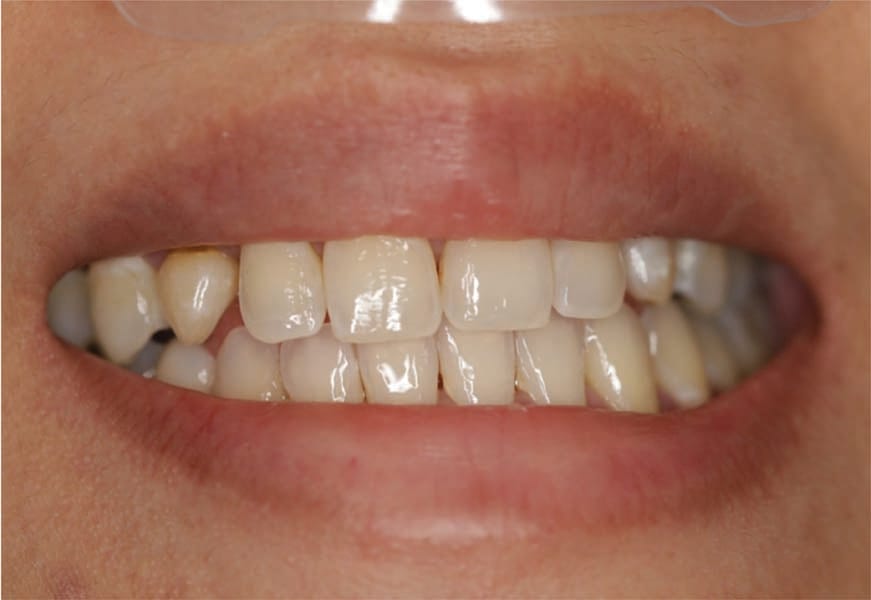

A 31-year-old Asian female presented for a consult. Her medical history was reviewed, and no health issues were noted. She indicated her last dental visit was 2 years ago and her chief complaint was that her deciduous canines felt loose and she was unhappy with her smile (Figure 1). Examination noted fair oral hygiene with light generalized calculus and moderate bleeding in the posterior with 4 mm probing on the molars. The deciduous canines were present bilaterally in the maxilla which were grade 1+ mobile (Figure 2). Cervical caries was noted on both deciduous teeth on the facial and also the distal of the left deciduous canine (Figure 3). Tooth No. 28 (right mandibular first premolar) was noted to be missing. The patient indicated the missing bicuspid never developed and the deciduous molar was lost in her teens. Physical examination noted a concavity in the vestibule apical to the gingival margin at both canine sites. A panoramic and bitewing radiographs were taken to evaluate the dentition and arches (Figure 4). Radiographically it was confirmed that the permanent maxillary canines were not present nor was the mandibular bicuspid. Further, significant resorption of the roots of the deciduous canines was noted.